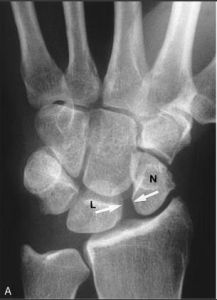

月骨周圍脫位者,月骨留在原位,其他腕骨向背側移位,並向橈側變位形成畸形。X線正位片顯示,脫位的月骨呈三角形(正常月骨應為四方形)。且投影與頭狀骨下端重疊。側位像顯示,月骨脫向掌側,半月形凹面也轉向掌側。